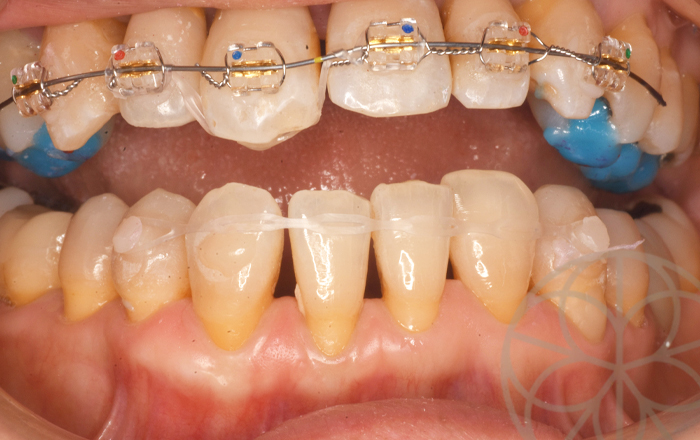

ブラケット、ワイヤーセット

インプラント

前歯の反対のかみ合わせを治すのに、上の歯の必要最低限のブラケット(歯につけている矯正装置)を設置し、ワイヤーをセットしました。上の歯の改善をする際、下の歯とのかみ合わせもありますので、下の歯の調整も必要です。

こちらも必要最低限の装置にて対応しました

ワイヤーセット後3ヶ月

ワイヤーセット後3か月治療を終了しました。

下の前歯のかみあせも変えることで、安定して、咬むこともできるようになりました。審美面の改善を最大の目的として行いますが、 やはり咬み合わせの改善が矯正治療の後戻り防止に役立ちますし、将来的に歯を失わないで済むベースになりますので、このあたりもこだわって治療させていただきました。

患者さまは、大変満足されており、われわれ治療者も大変うれしく思っています。

治療後写真

治療開始から3ヶ月で終了。

現在クリアリテーナーで保定中。

患者さんも大変満足されています。